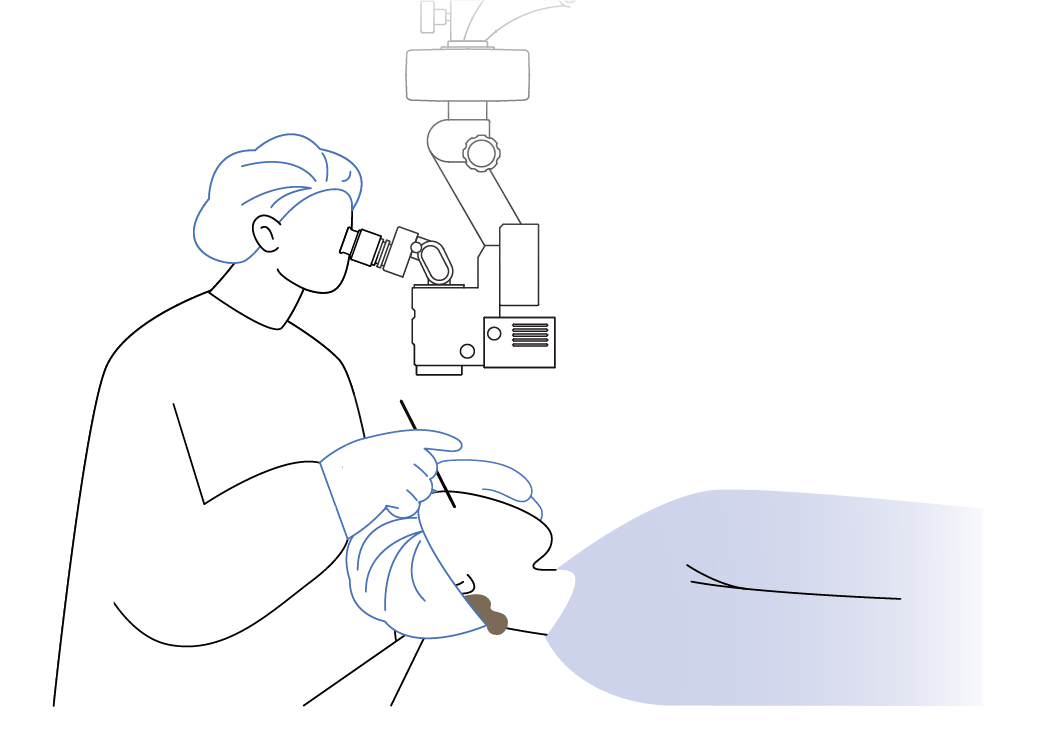

Operating Microscopes | 手術顕微鏡

OM-9

●白内障手術から網膜硝子体手術、外来処置まで幅広く対応

●アポクロマートレンズ、徹照照明でクリアな視野

最適な光学設計と高品質な光学システムにより、術中の視認性を最大限に高め、微細な組織や構造を鮮明に捉えることを可能にします。

徹照照明機構と高輝度LEDの融合

照明には、コントラストや色の再現性を重視した高輝度LEDを採用しています。徹照照 明機構により、眼底からの豊富な反射光で、白内障手術に不可欠な良好な徹照と立体的な観察像を可能にします。